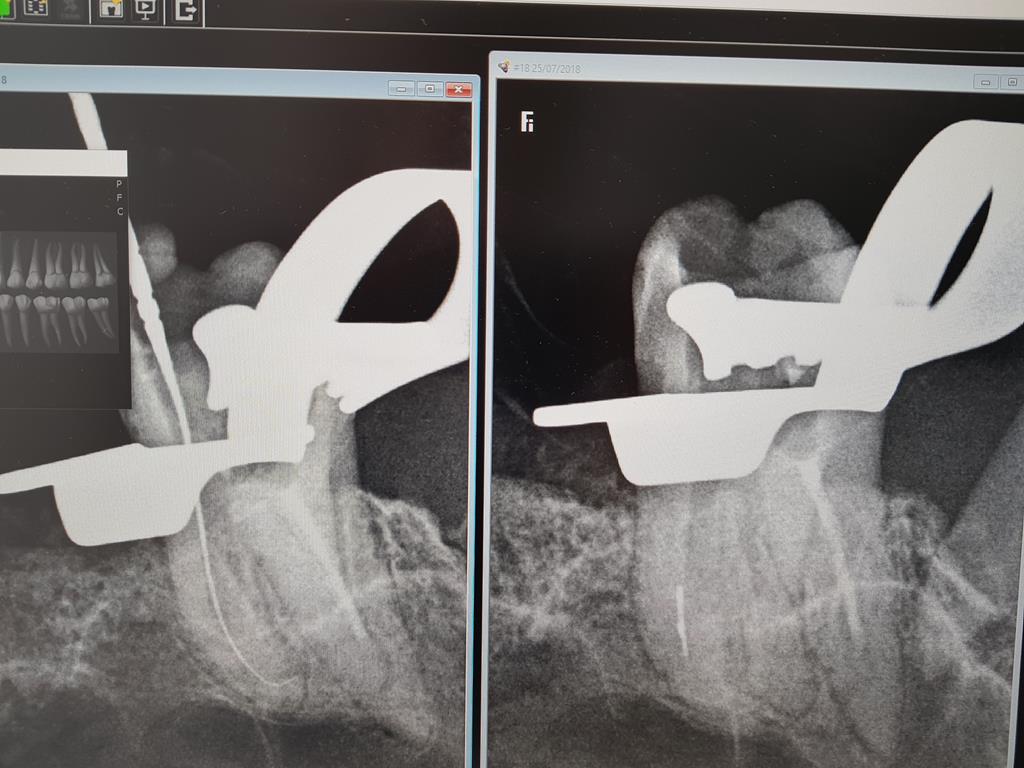

Endodoncja

Endodoncja to gałąź stomatologii zachowawczej zajmująca się leczeniem zębów martwych oraz objętych nieodwracalnymi procesami zapalnymi.

Informacja o wpływie na środowisko - RTG